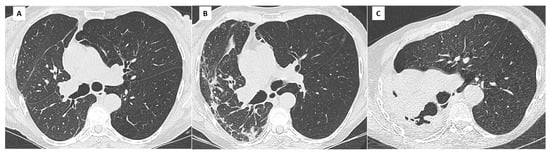

5. Restrictive Allograft Syndrome (RAS)